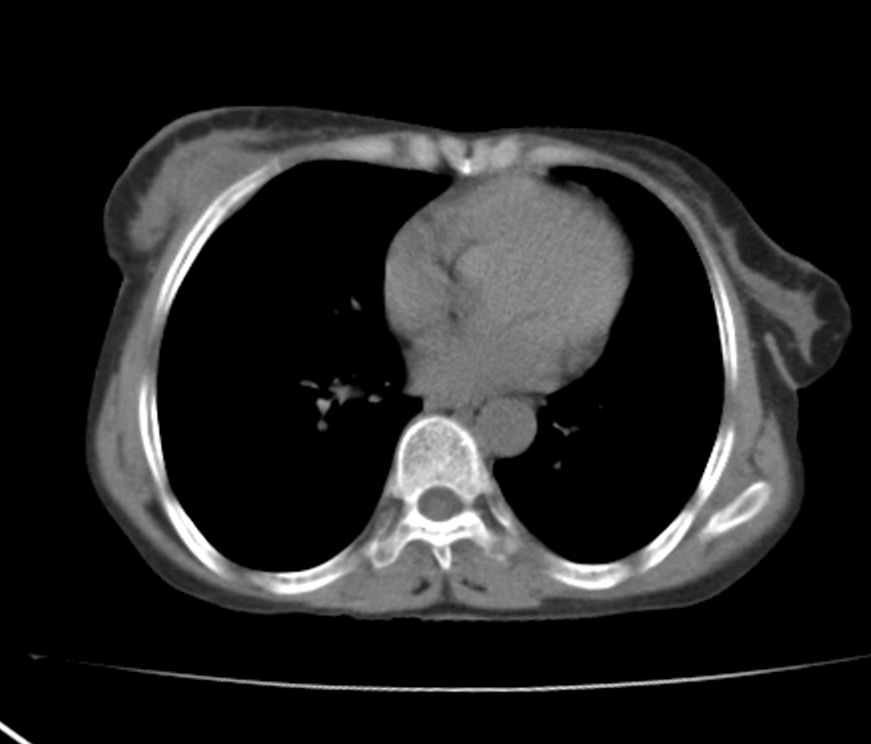

标题: CT21609:右乳包块1年,请各位讨论分析一下,乳腺CA, [打印本页]

标题: CT21609:右乳包块1年,请各位讨论分析一下,乳腺CA,

考虑---右乳癌并胸壁、肋骨、双肺转移。

考虑乳腺癌侵犯肋骨、胸壁及两肺转移可能性大。

右乳癌并胸壁、肋骨、双肺转移。

考虑右侧乳腺癌侵犯肋骨、胸壁及两肺转移。

支持考虑---右乳癌并胸壁、肋骨、双肺转移。

考虑右侧乳腺癌侵犯肋骨、胸壁及两肺转移可能。

考虑右侧乳癌并胸壁、肋骨及双肺多发性转移。

考虑右侧胸壁软组织肿瘤,肉瘤可能性大,双肺转移